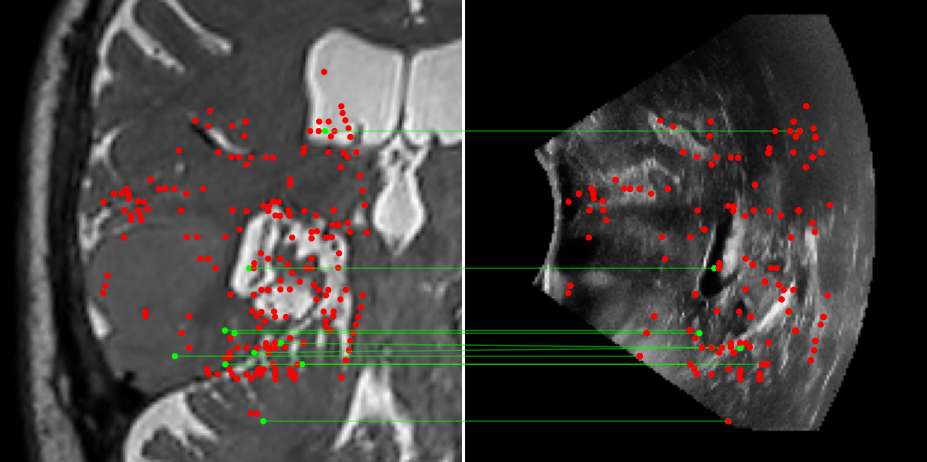

Figure 3: Examples of matching on three cases, one per column (MR on left and US on right). From top to bottom: SIFT+Cosine, MIND+Cosine, SP+Cosine, SP+LG, Ours+LG, Ours+Cosine. Correct matches recovered by each method are shown in green lines and mismatched are shown with a red dot.

To evaluate the performance of our model against existing image methods, we compared it to three approaches: SIFT [16], which remains the standard for keypoints matching, SuperPoint (SP) [3] built using a self-supervised learning approach and MIND [10], a modality-invariant descriptor for medical imaging, that although not designed for 1-to-1 keypoint matching, is extensively used for multimodal medical image registration through grid regularizing. We use SIFT and SP as keypoints detectors and descriptors, while we combine MIND with SP keypoints since it only provides a descriptor. We match these descriptors using both Cosine similarity and the deep neural network LightGlue (LG) [15] when possible (SP and Ours). Results reported in Table 2 and shown in Fig. 3 show that our approach outperforms these methods in terms of matching score, precision, and number of matched points. We only report results on three cases for readability reasons. Associating our descriptor with Cosine and LG reached similar performance depending on the metric.